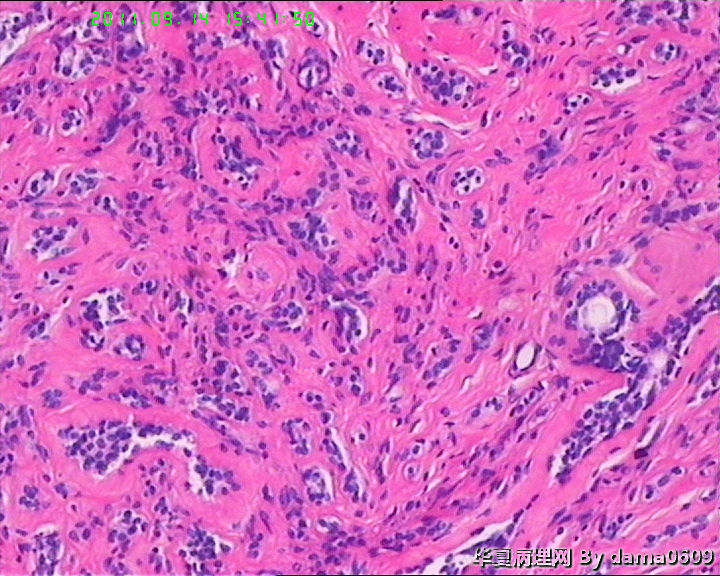

女,22岁,乳腺肿物,病史不详。

不整形软组织肿物一个,V:2.0x1.5x1.5cm。无包膜。切面实性,灰白色,小结节状,质中。

镜下结构复杂,图3、4、8、10、11、12、13、15、17、18、19、20为肿物中央区域,占标本大部分,图1、2、7、14为肿物边缘部分,图5、6、9、16、21为二者交界处。有点乱,不好意思,请老师别介意。

请教老师,诊断:硬化性腺病,可以吗??谢谢!!